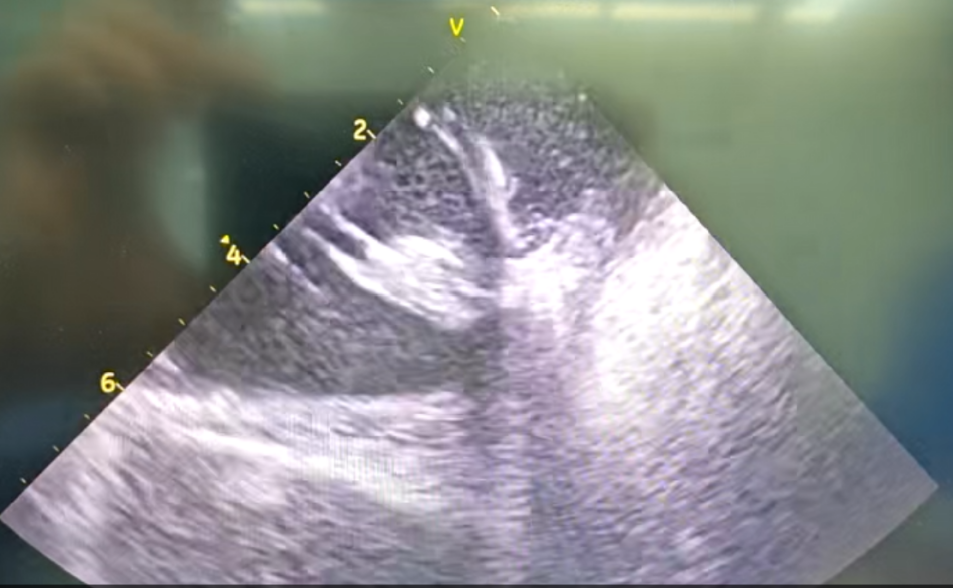

部分内膜室速靶点电位

右心室后组乳头肌室早电位

王林林主任医师谨慎操作,成功进入心外膜达到病变位置。术中,患者反复自发多形态室速,且转为室扑,同时出现血流动力学不稳定,需多次电除颤方能终止发作,标测难度极大。这就要求医疗团队必须在有限的标测时间内精准定位室速消融靶点,并结合心内外膜基质特征制定消融策略。经针对性消融后,患者未再自发室速,且室性早搏转为单一形态,经判定为右心室乳头肌来源,随即予以一并消融。术后经心室程序电刺激验证,室速未再被诱发。